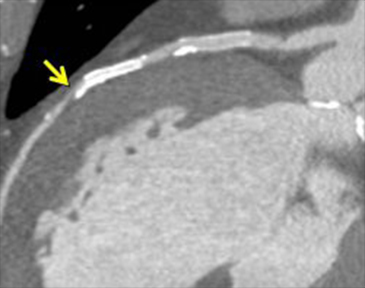

近年、心筋SPECTと心臓CTの融合画像により虚血性心疾患の包括的な診断が行われるようになってきています。本院では2007年7月より融合画像作成ソフトウェアを導入し一般臨床に用いています(図3)。

これにより冠動脈病変の部位と心筋虚血の関係をとらえ、適切な治療法の決定に役立てています。図4は労作性狭心症の症例です。ステントを留置した既往があり、最近になって再び狭心症症状が出てきました。左冠動脈前下行枝におけるステント留置部の遠位に狭窄病変がみられ、これが狭心症の原因となっている病変であることが分かります。

図4a 心臓CT

図4b SPECT/CT融合画像